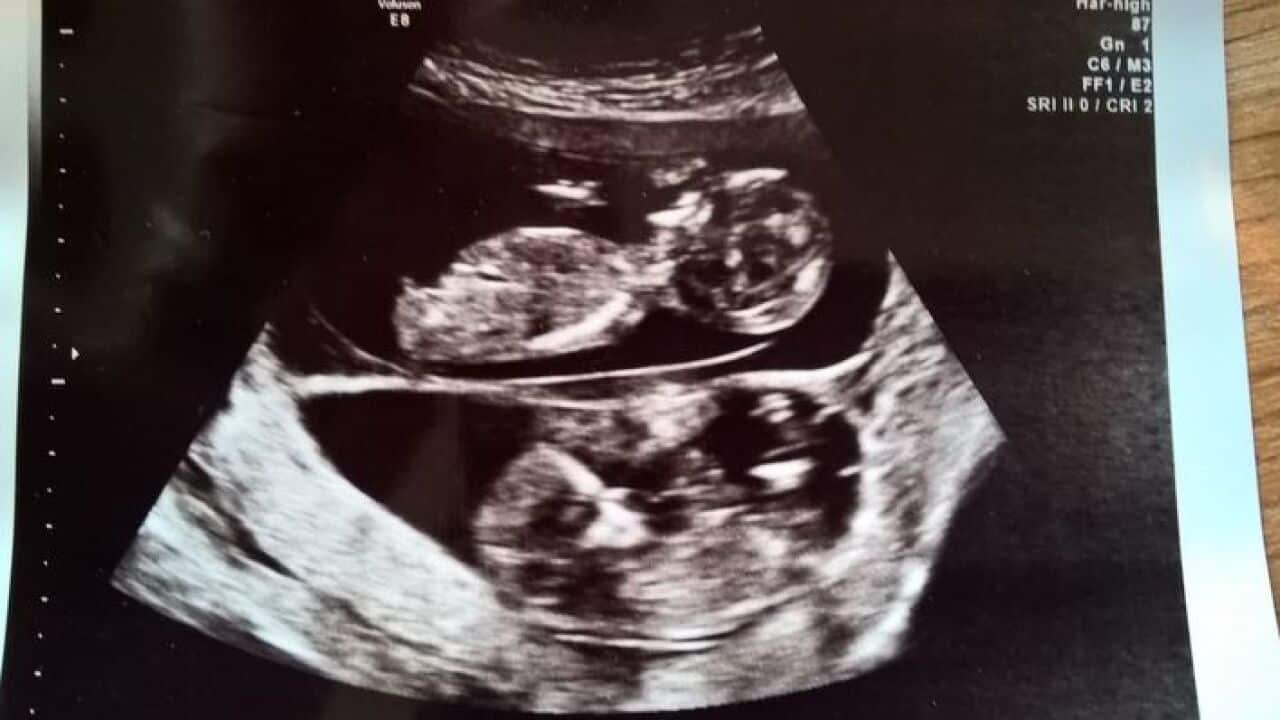

Twins as seen in an ultrasound scan Source: Getty Images

Two Queensland twins have made history after becoming the first pair of semi-identical twins in the world to be identified during pregnancy.